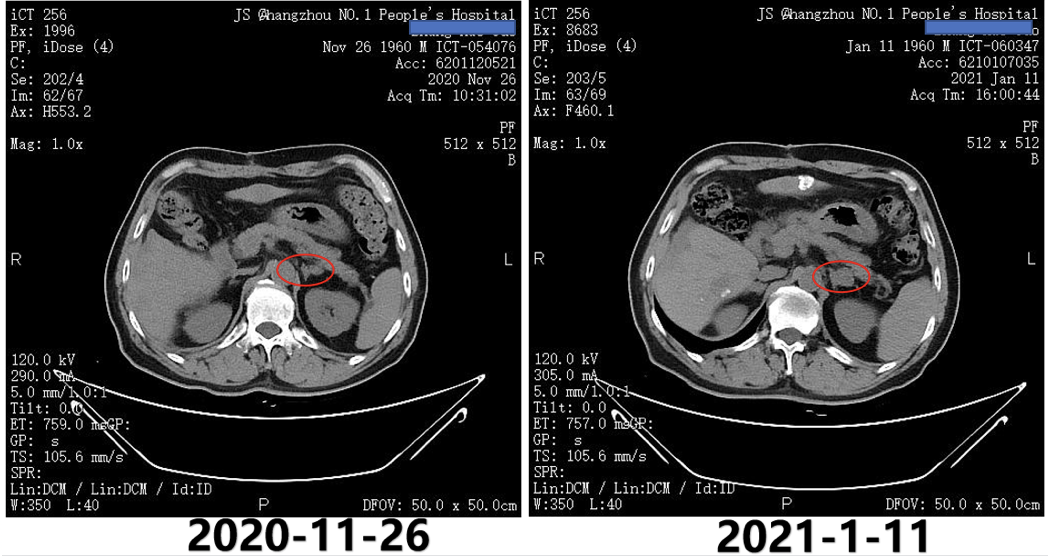

2020年12月2日即第1次TACE术后5天复查AFP为156.3ng/ml。2021年1月11日腹部CT提示,左侧肾上腺病灶较2020年11月26日明显增大,考虑转移(图3);2021年1月11日AFP明显升高为303.4ng/ml。

图3.2020年11月26日与2021年1月11日CT